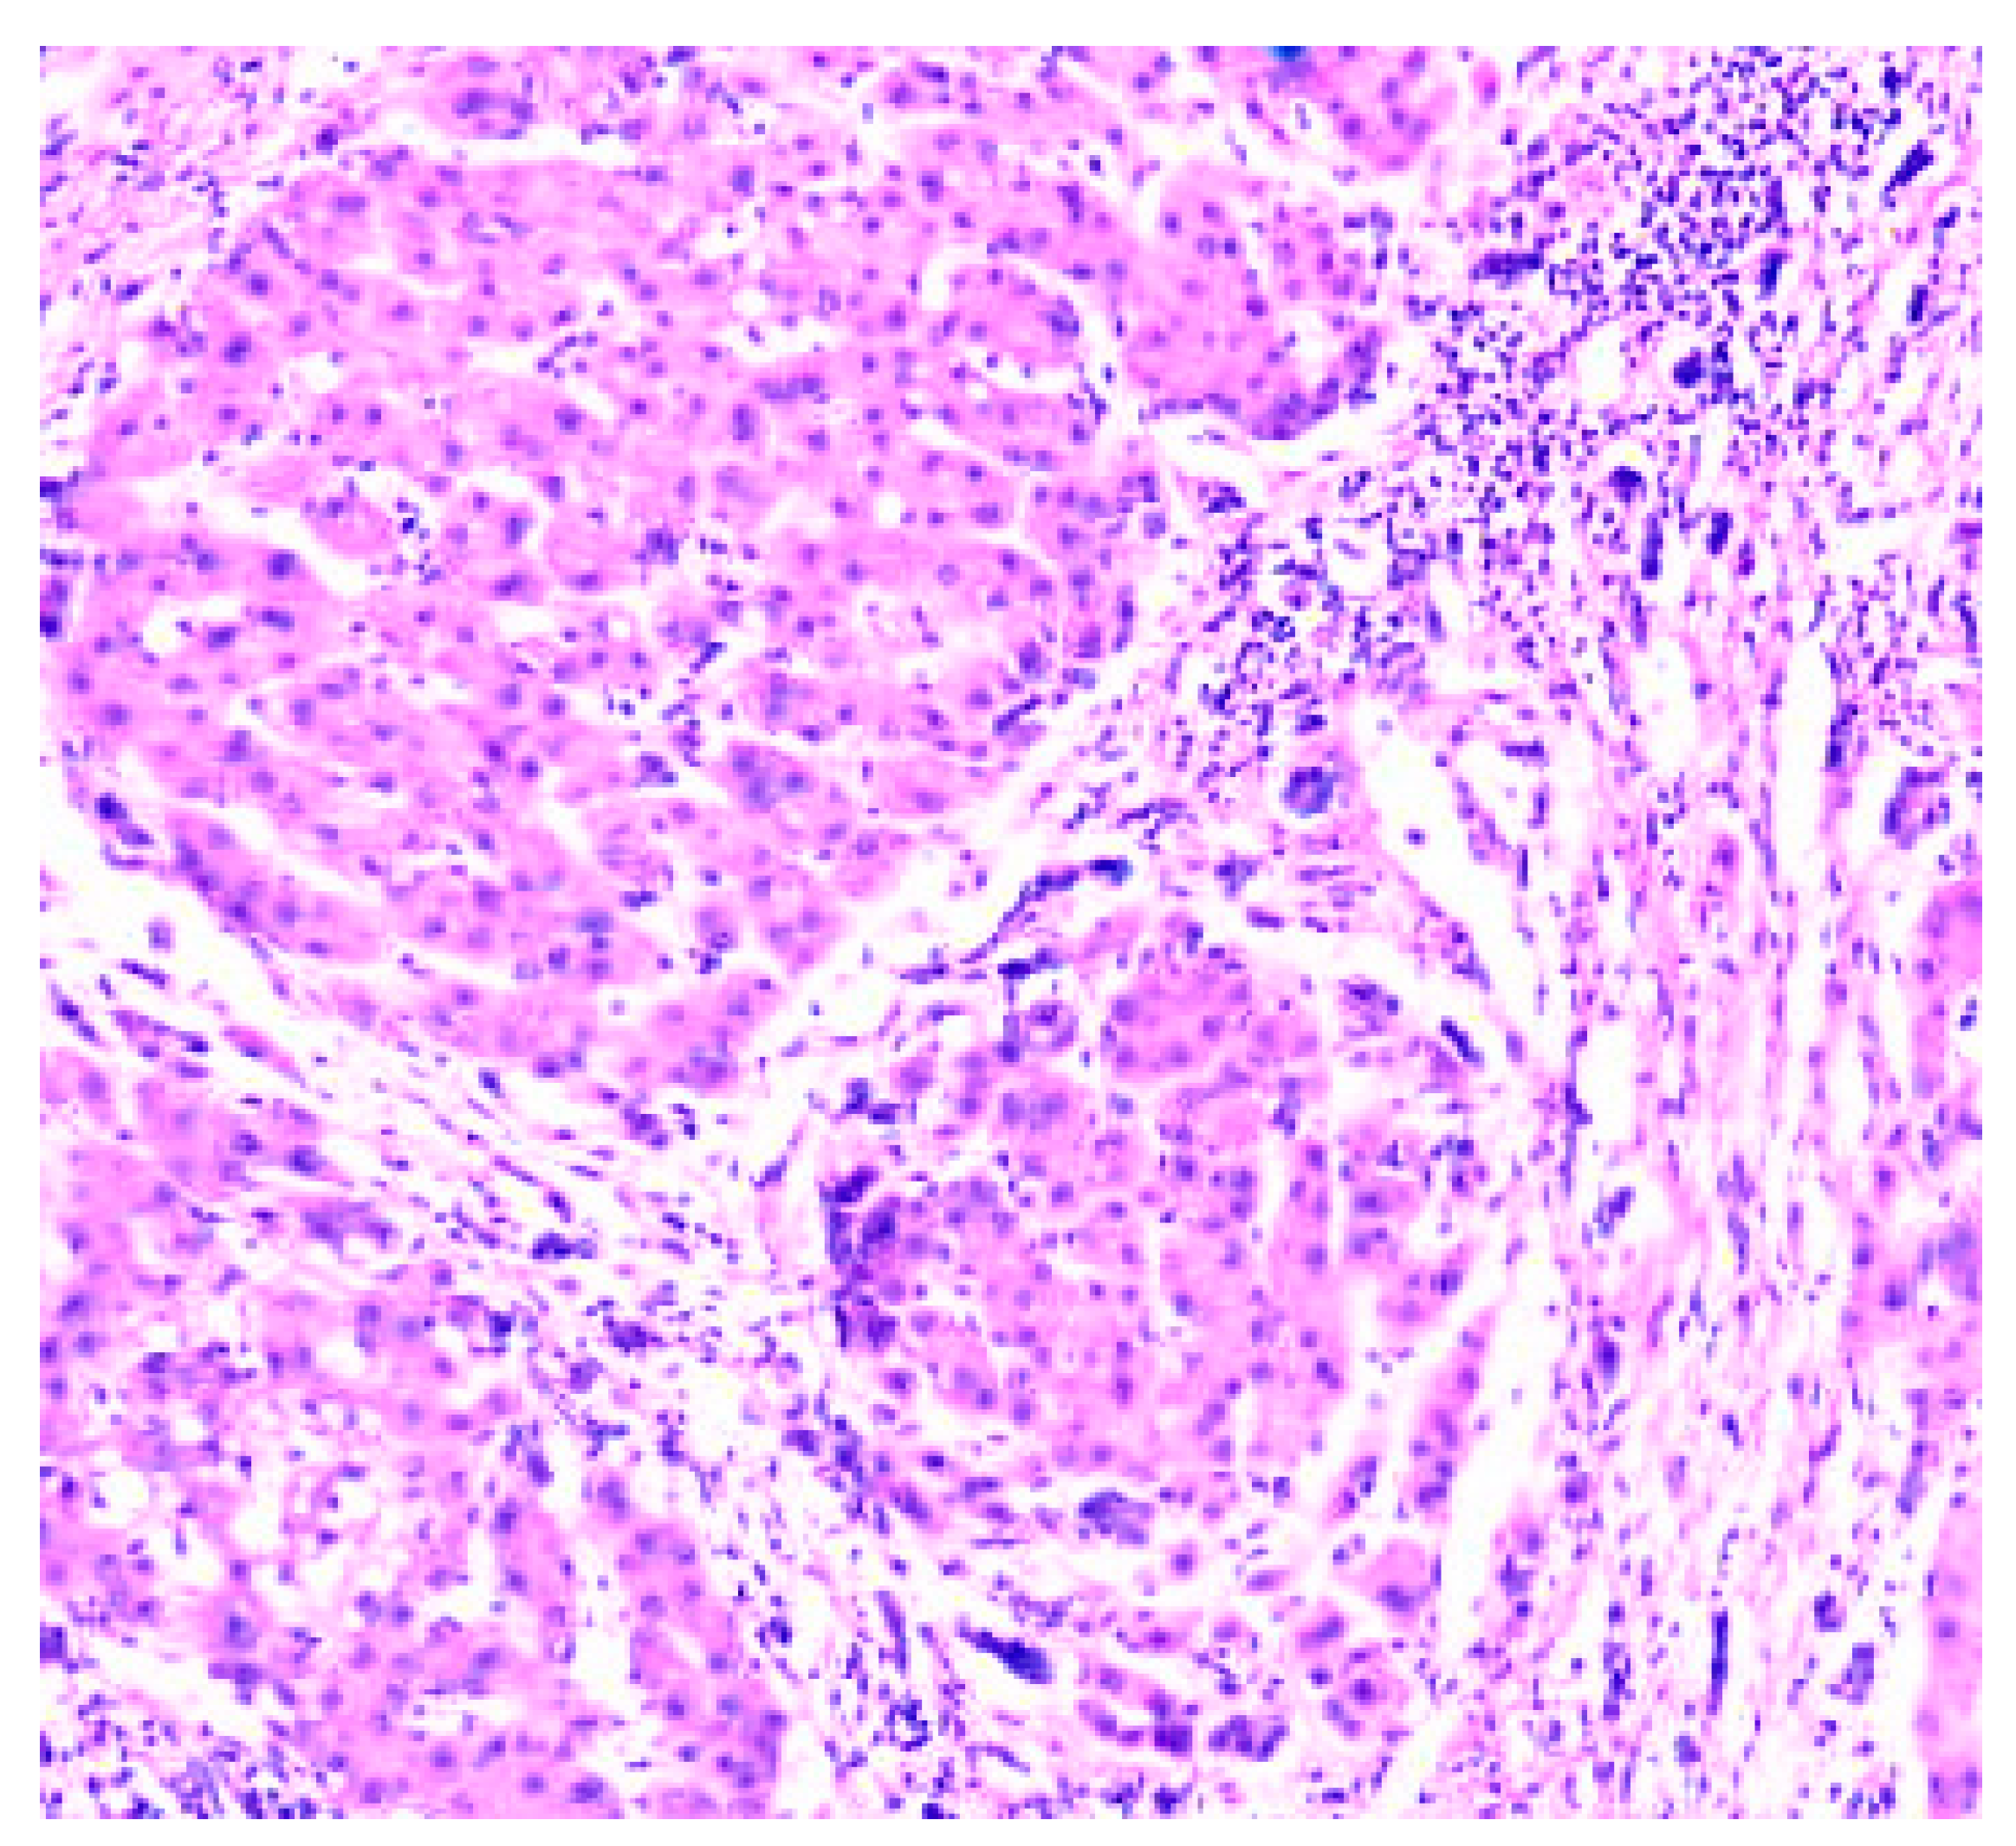

- Zone I is considered to be the periportal region of hepatocytes and are the best perfused and first to regenerate due to their proximity to oxygenated blood and nutrients. Implication in oxidative metabolisms.

- Zone II is defined as the pericentral region of the hepatocytes.

- Zone III has the lowest perfusion due to its distance from the portal triad. Implication role in detoxification.